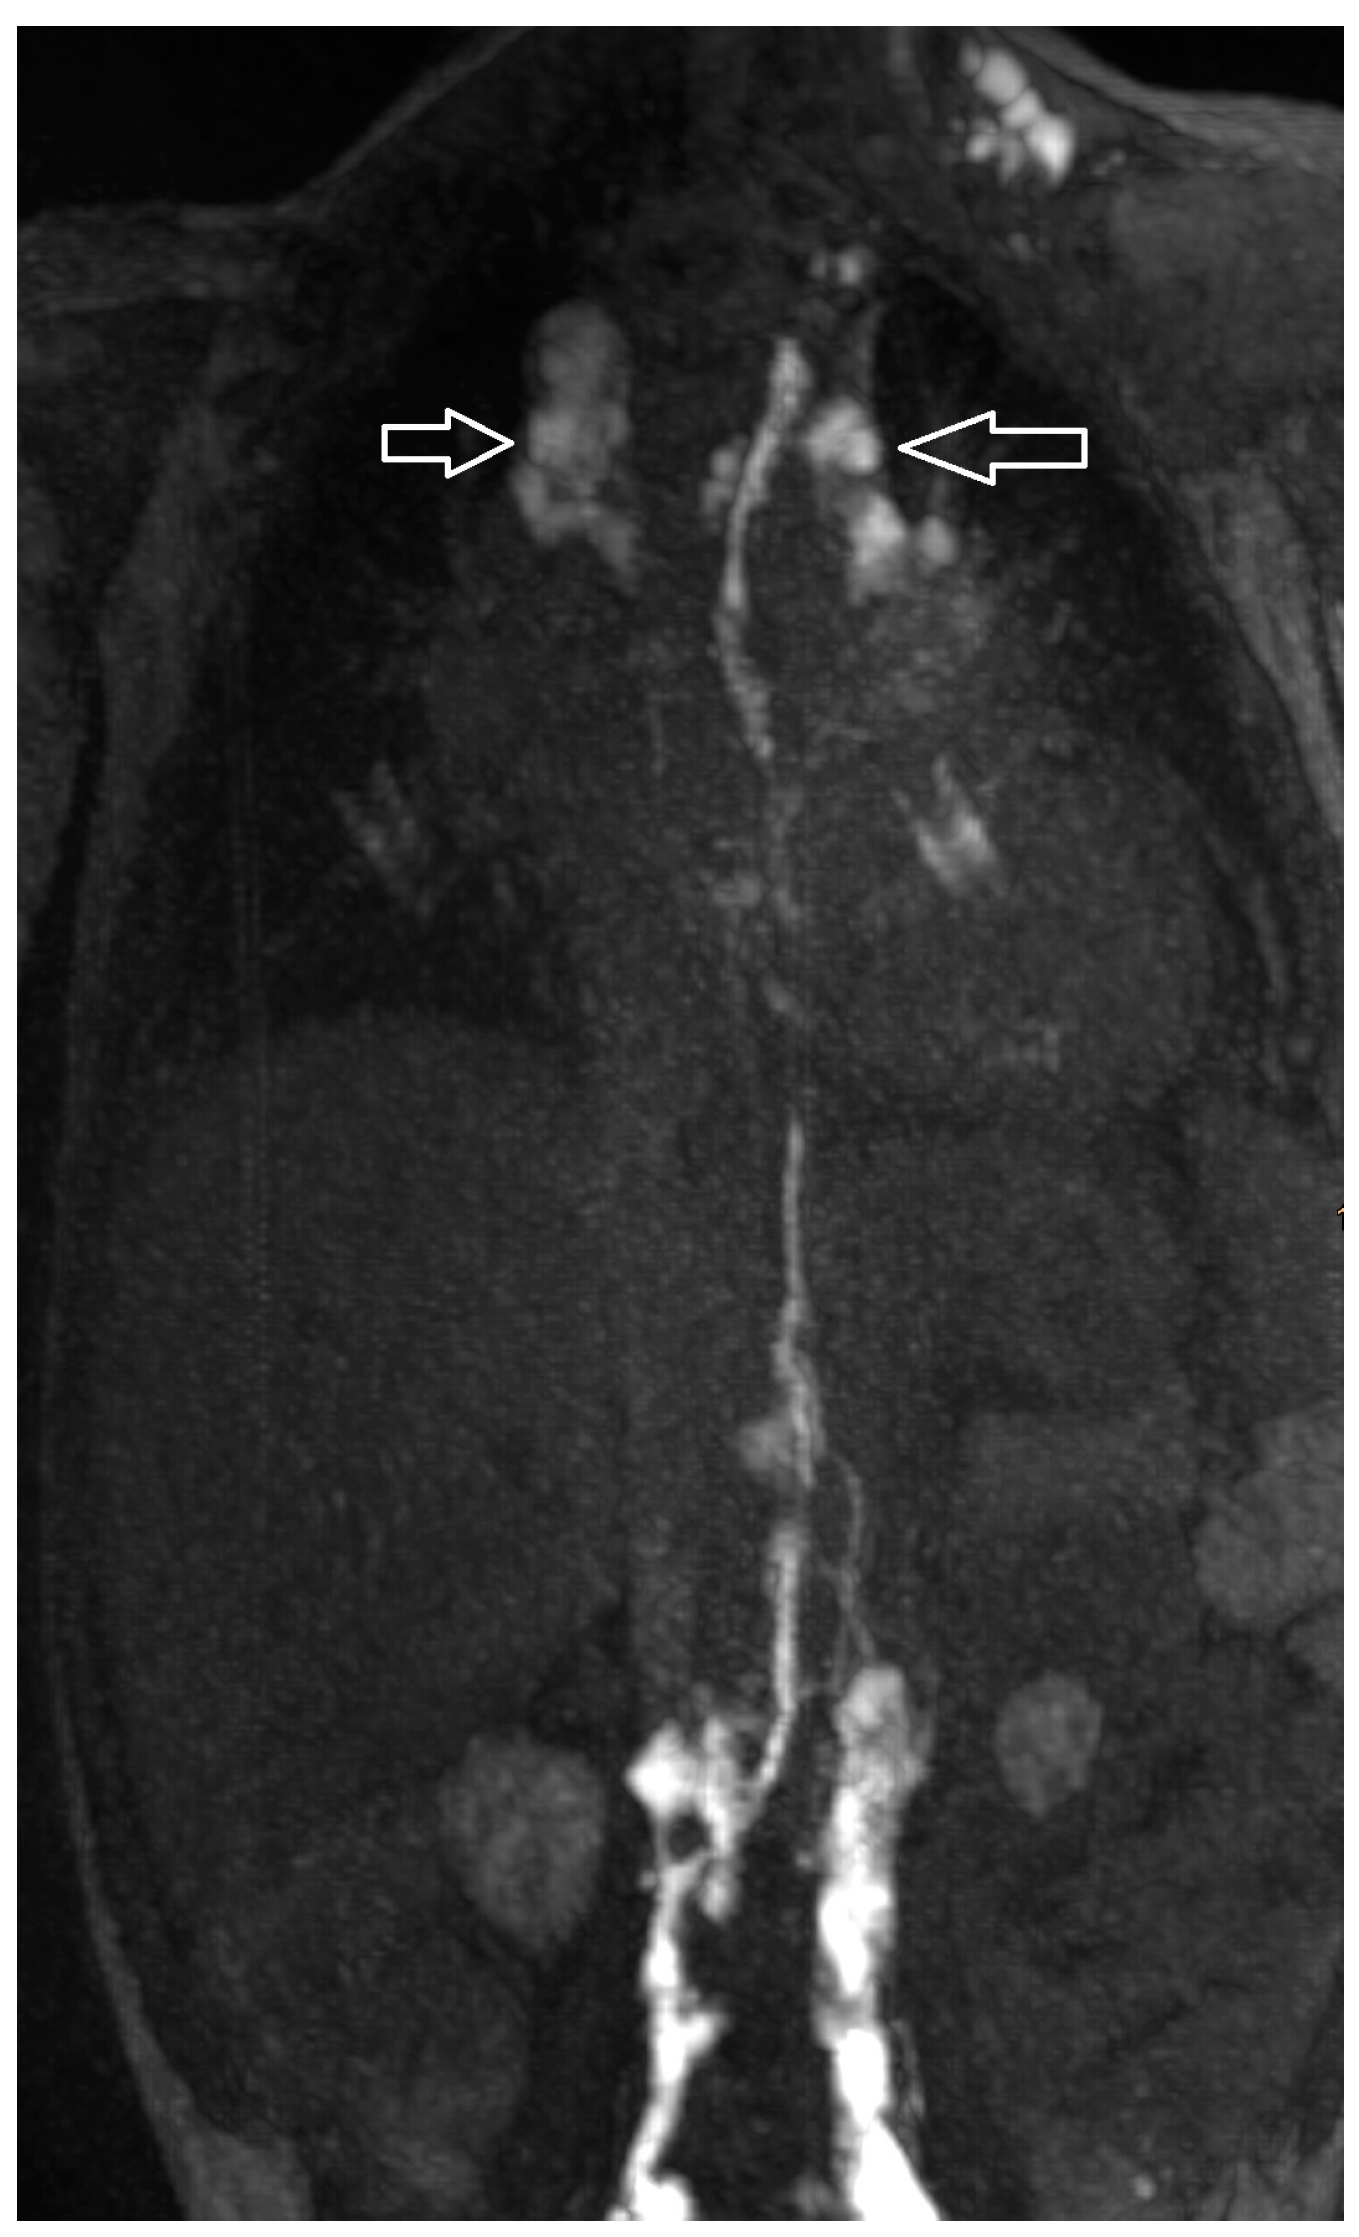

| 7 | 4 | increased signal neck, mediastinum and hilum, bilateral pleural effusion | TD intact, retrograde flow towards mediastinum and lung parenchyma bilateral | PLPS | TD bilateral TV 2 | CT revision, levosimedane | MCT diet, sandostatin, levosimedane | resolution (31/63/75)) |

| 11 | 3 | increased signal neck le > ri, mediastinum and hilum ri > le, pleural effusion | TD intact, retrograde flow towards mediastinum and hilum le | PLPS | no fistula visualized | diet modification | revision | resolution (42/62/71/20) |

| 12 | 4 | increased signal neck le > ri, mediastinum and hilum ri > le, pleural effusion ri > le, ascites | TD intact, retrograde flow towards mediastinum, hilum, lungs ri > le | PLPS | no fistula visualized | MCT diet, somatostatin | Glenn takedown | resolution (84/142/208/37) |

| 21 | 4 | increased signal mediastinum, hilum, lung le > ri | retrograde flow from TD with diffuse mediastinal and peribronchial perfusion | thoracic vertebrae 4–10 to left mediastinum | MCT diet, macitentan, alteplase inhalation, salbutamol, diuretics | glue embolization of TD | cast free after intervention (FU 1 a 4 m) tapering off sildenafil |

| 22 | 4 | increased signal (mediastinum), hilum/lung ri | retrograde lymphatic flow to mediastinum and lung parenchyma ri | from hilum to ri lung | fat reduced diet, sildenafil, alteplase/ fluticasone inhalation | selective glue embolization of 2 branches of TD | cast free after intervention (FU 4 a), cessation of fat-reduced diet, |